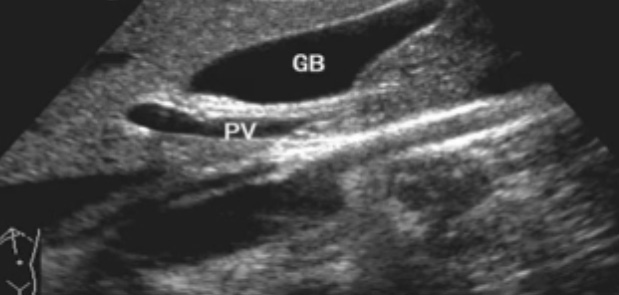

肝內(nèi)膽管-無(wú)膽管擴(kuò)張的情況下,超聲一般只能顯示膽管的一、二級(jí)支,不能顯示二級(jí)以上的肝內(nèi)膽管肝外膽管(聲像圖上大致分為兩段)上段與門靜脈伴行,位于門靜脈主干的右前方;下段與下腔靜脈伴行并延伸進(jìn)入胰頭背外側(cè)。膽道、肝動(dòng)脈與門靜脈的關(guān)系。